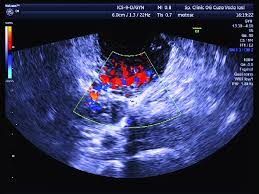

Transvaginal Ultrasound From A 28 Year Old Woman With A Left Ectopic Download Scientific Diagram